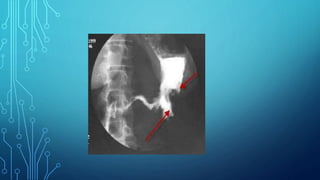

6. Fluoroscopy of the stomach: the main

symptoms are filling defect, the presence of

aperestaltic zones. Apithetic relief of the

mucous membrane, local thickening or

breakage of the folds of the mucous membrane.

Diagnostics 1. Complaints 2. Anamnesis 3.Palpation 4. Study of gastric contents 5. Blood test 6. Fluoroscopy of the stomach: the main symptoms are filling defect, the presence of aperestaltic zones. Apithetic relief of the mucous membrane, local thickening or breakage of the folds of the mucous membrane. 7. Gastroesophagoduodenoscopy 8. Biopsy